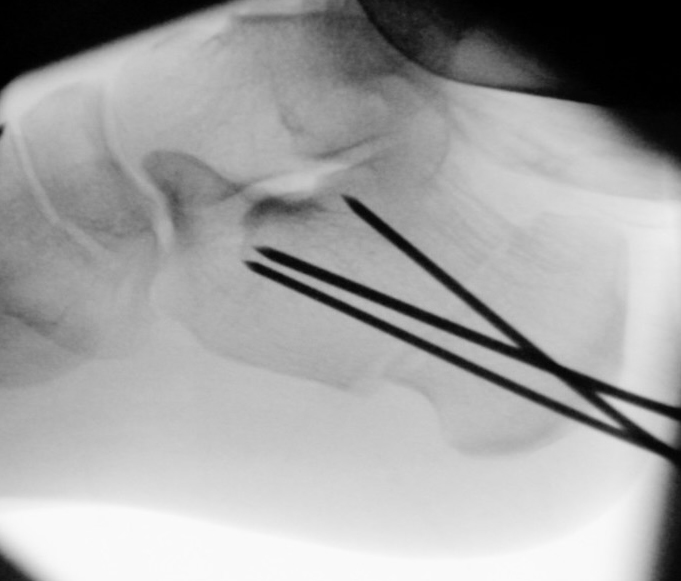

Zusätzlich schränken Wachstumsfugen die Wahl der Osteosynthese ein. Eine die Fuge kreuzende Osteosynthese ist ausschließlich mit Kirschner-Drähten möglich (Abb. 3).

Abb. 3 a-j: Beispiel einer Calcaneusverschiebeosteotomie mit offenen Wachstumsfugen und der entsprechenden Osteosynthese mit Kirschner Drähten. Lokalisation der Osteotomie (a), Lage der Fräse (b-d), Drahtlage mehrere Ansichten (e-h), Heilung der Osteotomie 4 Wochen postoperativ und Entfernung der Drähte (i-j).

Zum Lesen der Bildbeschreibung und zur Vollansicht bitte die Bilder anklicken. Bilder: A. Helmers.